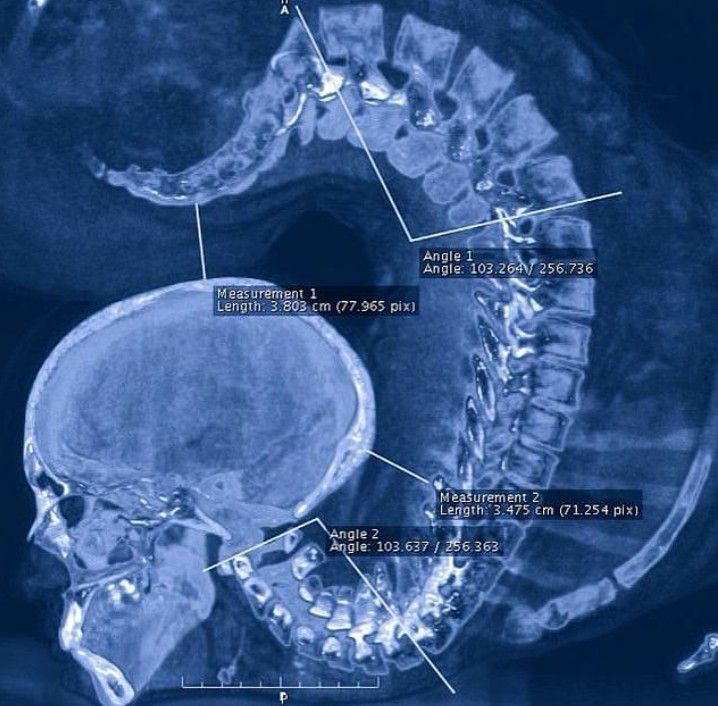

here you can see the X-ray of a contortionist girl performing an exercise!! What you’re looking at is an x-ray of an individual in an extreme pose of spinal extension! Contortionists excel at extreme physical flexibility. They twists and bends their body into strange and unnatural positions. Note how the thoracic spine stayed almost completely straight. Contortionists, gymnasts, dancers, yogis, all of these athletes excel at their sport with exceptional spinal flexibility. But at what cost? The spine forms the central axis of the skeleton, supports the skull, and gives attachment to the thoracic cage, pectoral girdle, and upper limb. It combines strength with great flexibility as it has many joints close together. Movements of the spine are possible due to intervertebral discs, and with the fulcrum of movement occurring primarily around the nucleus pulposus. Specialized motion occurs at the atlanto-occipital and atlantoaxial joints, which do not contain a disc. Flexion and extension are common to all parts of the spine; a significant degree of flexion/extension can be achieved at the atlanto-occipital joint, cervical and lumbar spine, but is restricted in the thoracic spine. Lateral flexion is free at the atlanto-occipital joint, cervical and lumbar spine, but less free in the thoracic spine. Rotation is greatest at the specialized atlantoaxial articulations, and to a lesser degree in the cervical and lumbar spine. A medical publication from 2008 suggests that long-term damage to the spine is common in long-term contortion practitioners. A study of five practitioners using magnetic resonance imaging (MRI) by Peoples et al. documented limbus vertebrae, intervertebral disc bulges, and disc degeneration. Three of the five practitioners also reported back pain.